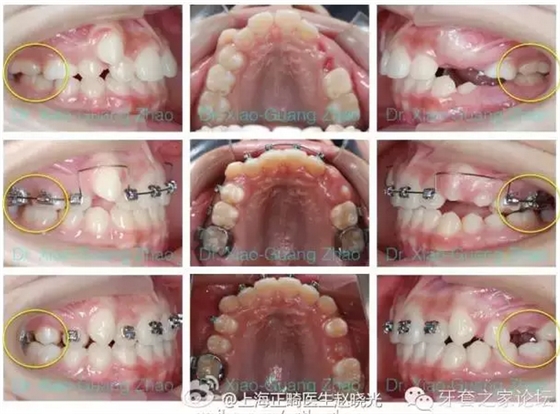

推磨牙向后一般是指推上頜磨牙向后,該技術在后牙咬合關系輕度錯位,且上前牙存在輕度前突或輕中度擁擠的情況下使用。

如果能在上頜第二磨牙萌出之前開始治療,效果能夠更好。

(一)擺式矯治器結合固定矯治器,1992年有Hilgers發(fā)明。其特點是效果明顯,但推磨牙向后的作用多來源于磨牙的向后傾斜,因此比較容易在固定矯治階段復發(fā)。歡迎參見2005年4月我發(fā)表在“華西口腔醫(yī)學雜志”上的文章。

(三)支抗種植釘結合固定矯治器。特點是不依賴患者配合,效果比較肯定,但是有一定的創(chuàng)傷性。